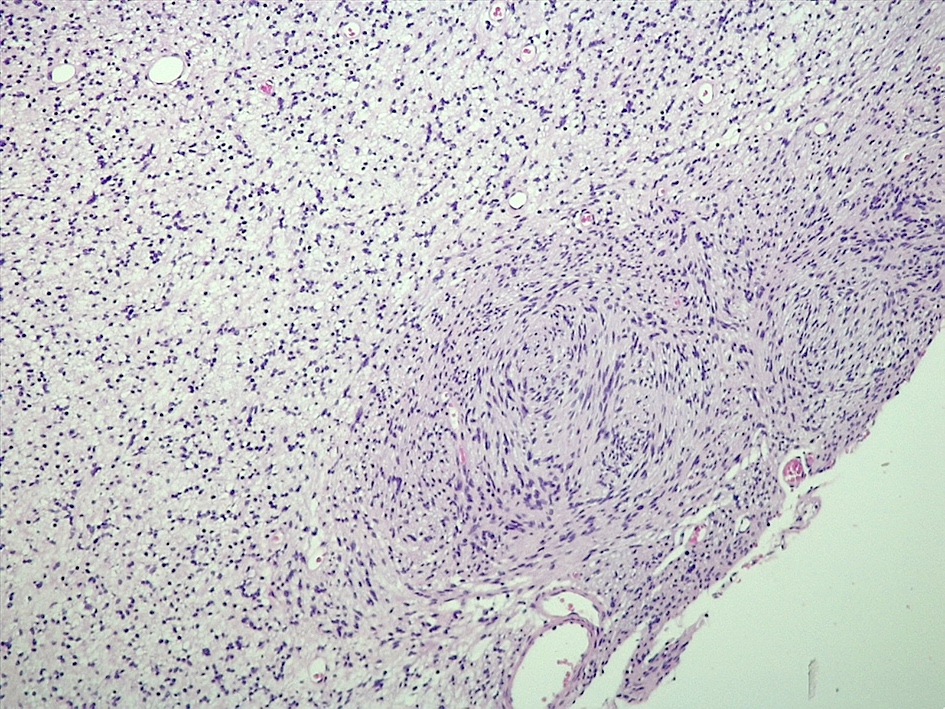

Microscopic (histologic) description

- Spindle cell tumor (usually biphasic) and composed of compact hypercellular areas (Antoni A tissue) showing nuclear palisading (Verocay bodies) and loose microcystic areas (Antoni B tissue) with collection of lipid laden histiocytes and thick walled hyalinized blood vessels (Surg Neurol Int 2020;11:454)

- Lymphoid aggregates maybe seen peripherally or in a subcapsular distribution

Microscopic (histologic) images